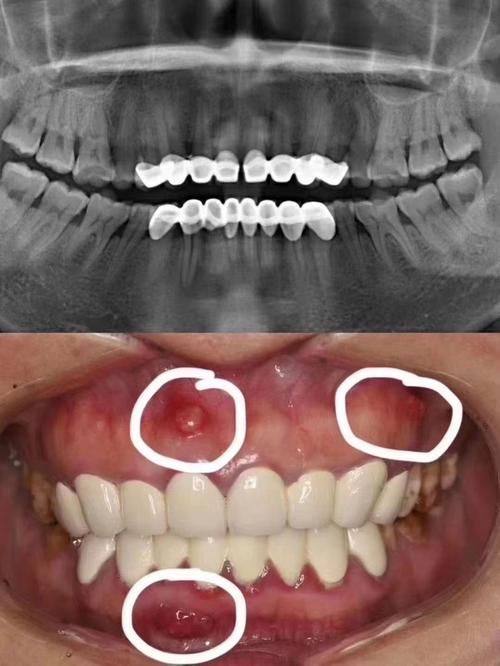

患者张女士 种植牙修复实例

“我之前因为牙槽骨太薄,跑了好几家医院都没法做种植,后来找到康斯坦丁医生。他耐心给我讲解了GBR骨再生的治疗方案,整个手术过程特别顺利,术后修复也比预想的快特别多,现在终于能正常吃东西了,真的特别感谢他。”